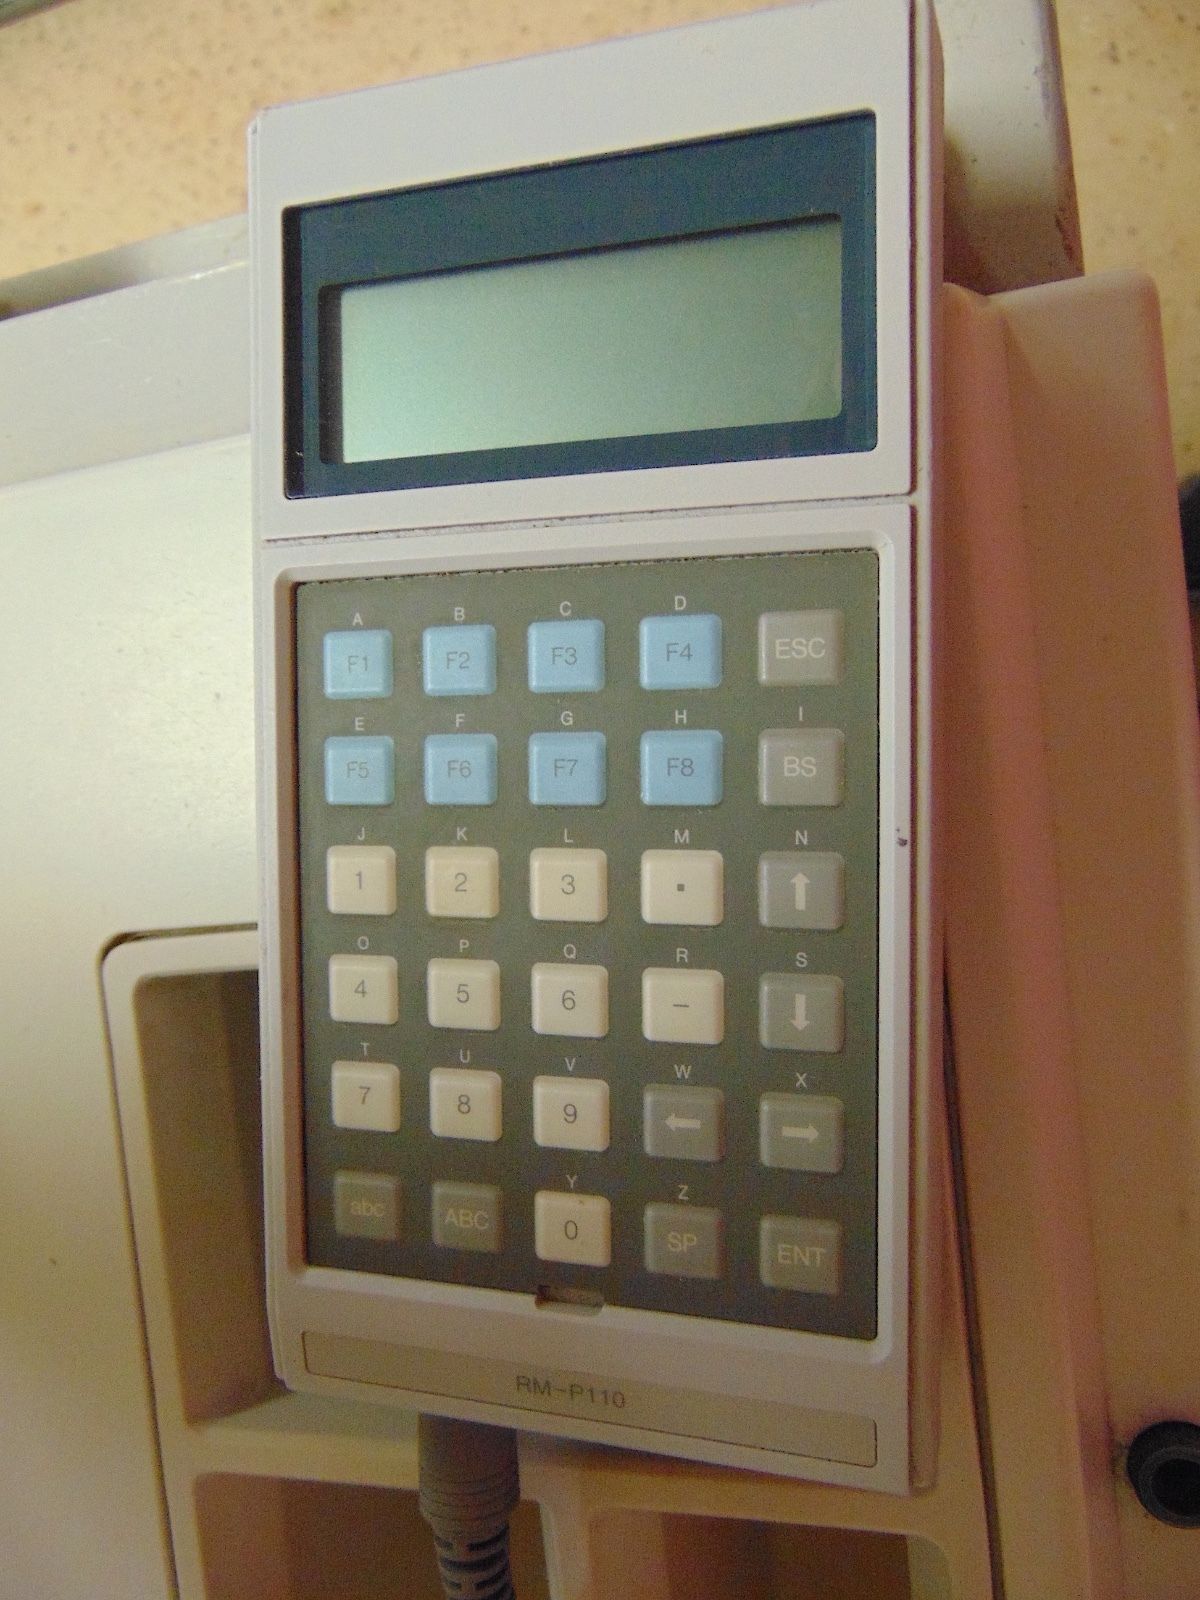

Seller Notes:âThe unit powers on and the monitor works good. Comes with a remote control unit and a functioning ultrasound probe. Unit is in good cosmetic condition but does show wear from being used.â